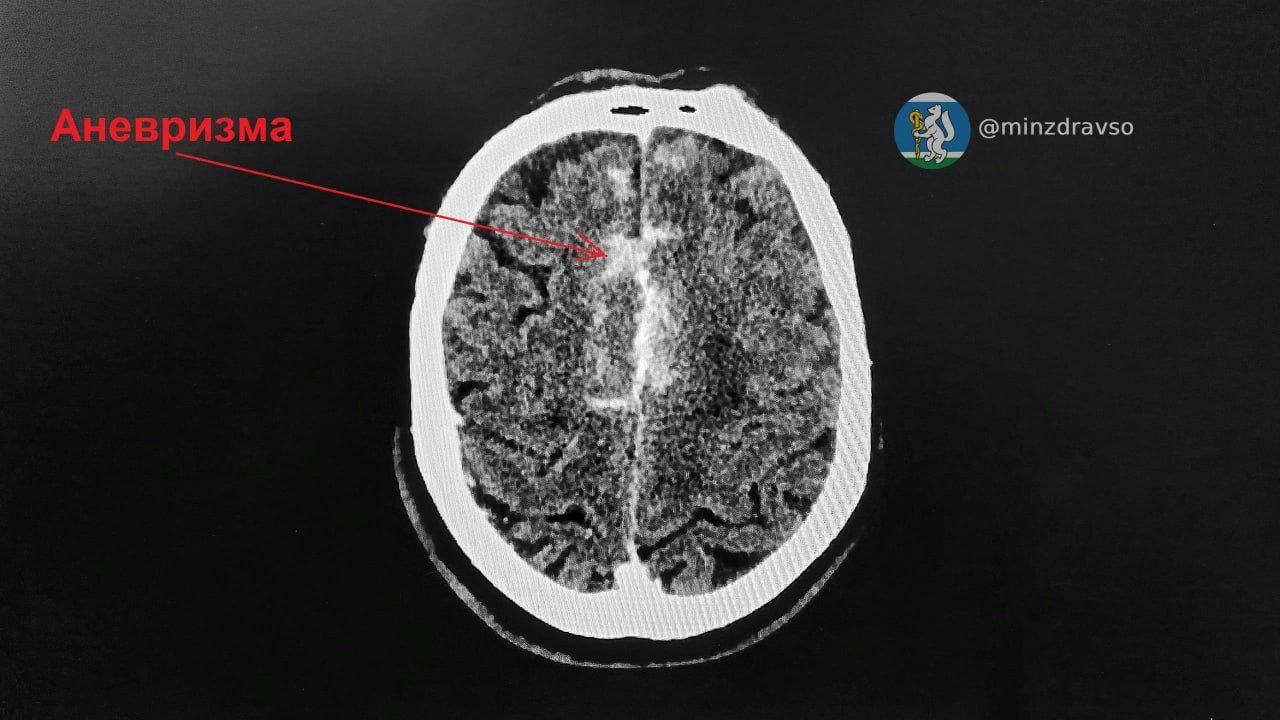

Медики доставили мужчину в состоянии комы в ГКБ №14. Специалисты провели обследования и выявили аневризму передней соединительной артерии и массивное кровоизлияние. Чтобы спасти пациента, решено было сделать ему срочную операцию в Региональном сосудистом центре на базе ГКБ №40, куда пациента экстренно доставили.

«С помощью миниатюрного титанового зажима врачам необходимо было пережать сосуды, питающие мозг, но надолго отключать кровоток нельзя. На основные действия нейрохирургу Павлу Ошуркову потребовалось три минуты, и операционная бригада буквально под тиканье секундомера успешно справилась с задачей», — сообщили в минздраве региона.